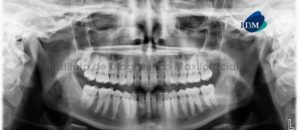

Paciente masculino de 61 años acude al Instituto de Diagnostico Maxilofacial para evaluación general de las piezas dentarias. A la evaluación panorámica se aprecia a